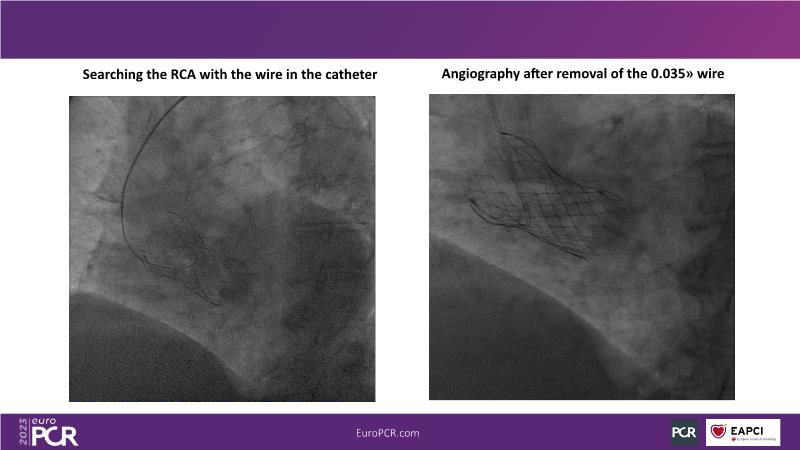

Discover the key factors to consider in selecting the optimal valve and implant technique for transcatheter aortic valve implantation (TAVI) to achieve optimal procedural outcomes. Gain insights into the impact of device choice and implantation technique on coronary access following TAVI and learn valuable strategies for tailoring your TAVI technique to complex scenarios, including bicuspid aortic valves, large and calcified anatomies, and ensuring coronary access.

- To appreciate the impact of device choice and implantation technique on coronary access after TAVI

- To learn how to tailor your TAVI technique to complex situations: bicuspid aortic valves, large, calcified anatomies and coronary access